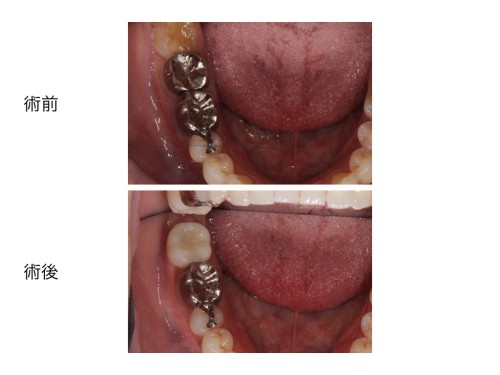

前歯のインプラント治療を行った方の術前術後です。

この方の初めて来院された時のお写真です。

今まで歯科に行ってはどうにもならないと言われてきた患者さんです。

歯磨き指導などは今まで受けたことがなくこのまま悪くなるのを待つだけと言われていたそうです。

レントゲン写真ですが歯周病の重度の進行があります。

まず大事なのは、きちんと歯磨き出来る様にすることです。

だいぶ歯茎が引き締まってきました。

想定していた位置にインプラント治療ができました。

インプラント治療を行ったのち仮歯を作ります。

仮歯でしばらく噛み心地を確認してもらった後、セラミックの歯に置き換えていきます。

患者さんはとても満足され、見た目も良く何でも噛むことができる様になりました。